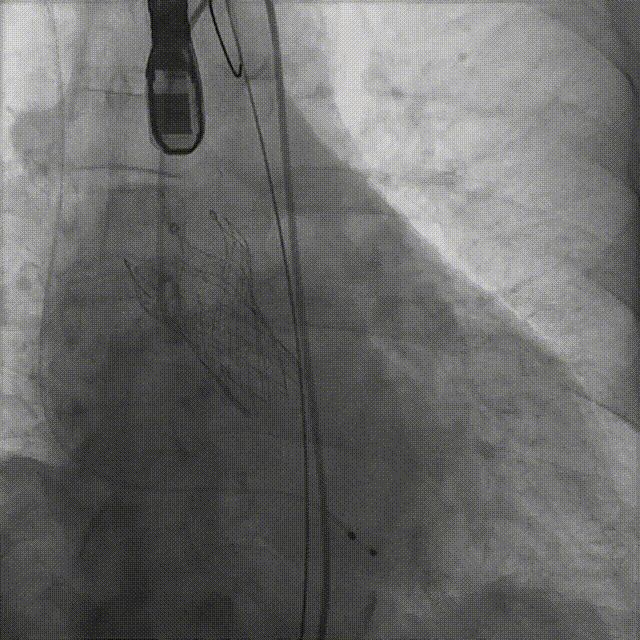

病例概览

患者病史 男性,74y, 因 “发现心脏瓣膜病 1 年,加重伴喘气半年” 入院。门诊检查显示主动脉瓣重度AS并伴轻-中度AR。患者基础疾病较多:胸腹主动脉多发穿透性溃疡、心功能III级等,手术指征明确,但风险极高。 术前CT LVOT- Annulus 倒梯形,对植入瓣膜有挤压位移风险,Annulus直径23.7mm,瓣叶增厚,钙化集中在无冠窦边缘。 左冠脉开口高度可,瓣叶不长、窦部空间较大,无冠脉风险;室间隔膜部较短,有一定PPI风险,心脏角度37.9°;心室较小,有一定循环崩溃风险,术前注意补液。 术前造影角度及入路:血管入路散在钙化、无迂曲;主动脉弓条件好、双侧股动脉直径大、右股穿刺点侧壁存在环形钙化 左右重合位:RAO 7° CAU 21° 右窦中心位:LAO2 1° CAU 1° 手术策略 20mm球囊预扩后植入AV26瓣膜,同时做好预防循环崩溃、传导阻滞的应急预案。 术中挑战 1)球囊预扩:20mm球囊预扩时无明显 “腰征”,但存在少量反流,提示瓣膜钙化与解剖结构对扩张的阻力不均 2)首次释放偏差:第一次定位释放时,瓣膜在 “开花” 过程中下滑约 3mm,工作位观察显示小弯侧瓣周漏较多(深度超过完全覆膜区),需二次调整。 3)二次精准定位:以猪尾导管为参照,将定位点调整至 “猪尾 - 2mm” 处,结合真实窦底深度(较深)重新释放,最终瓣膜位置稳定,瓣周漏显著减少。 术后即刻效果: 瓣膜形态良好,跨瓣压差从术前的 67mmHg 降至 6mmHg,且无明显瓣周漏,冠脉开口通畅; Commisural Alignment 术后即刻超声: Prostyle A®预装干瓣——助力临床最优化解决方案: √ 平衡的径向支撑力:特殊的解剖结构下位置形态良好,术后跨瓣压差大幅降低,血流动力学改善明显; √ 80%可回收设计:支持术中二次调整释放位置,保证精准释放; √ 平衡的收腰设计&Commissural Alignment设计: 为患者后期冠脉PCI保留了生命通道;